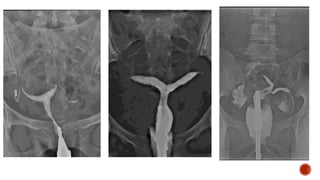

It is the radiographic

examination of urinary

tract including renal

parenchyma, calyces

and pelvis after

intravenous injection of

contrast media.

1. Screening of the entire urinary tract especially in cases of haematuria or pyuria.

2. Diseases of the renal collecting system and renal pelvis

3. Differentiation of function of both kidneys.

4. Abnormalities of the ureter.

5. Obstructive uropathy- IVU is the gold standard.

6. TB of the urinary tract

7. Calculus disease.

8. Potential Renal Donors.

9. Prior to endo-urological procedures and surgery of urinary tract.

10. Suspected renal injury.

11. Renal colic or flank pain.